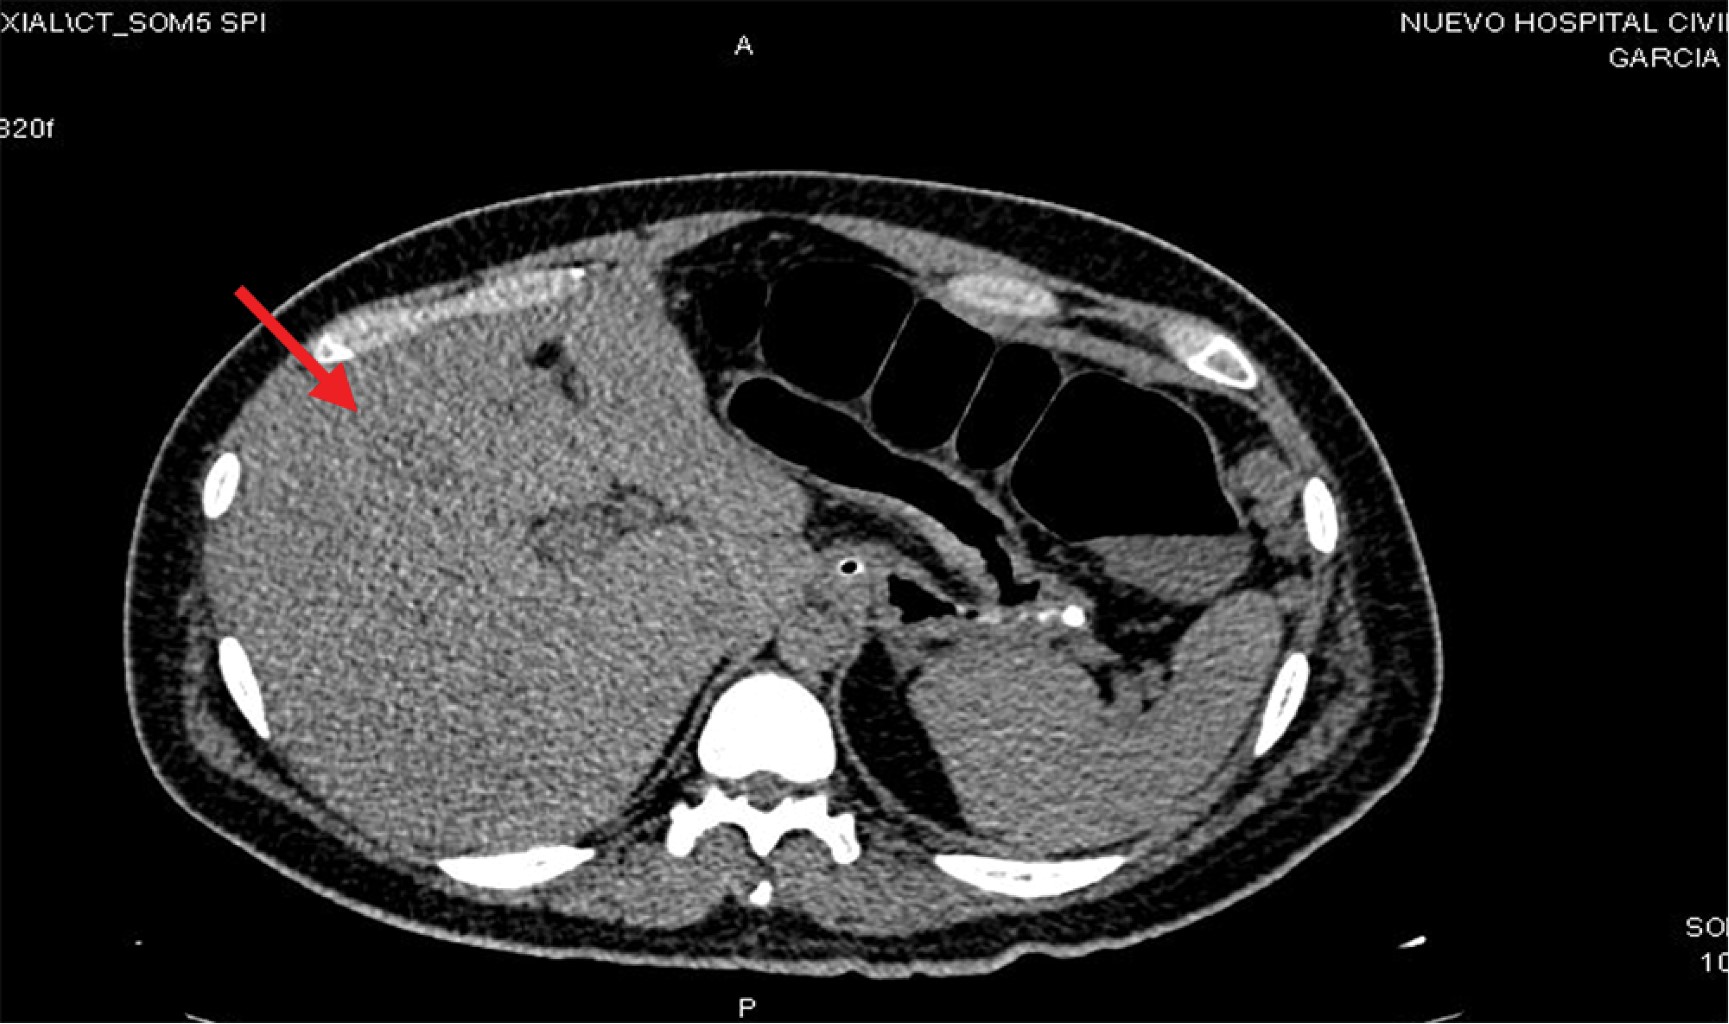

Stage IV rectal cancer in a 25-year-old patient. Report of a case

Introduction: rectal cancer can occur in young patients with no family history, so it is important to assess screening studies in the young population. Clinical case: 25-year-old male with no family history, goes to the emergency department due to a distal bowel obstruction with a history of 30 kg weight loss and diarrhea of six months' duration, imaging studies with an upper rectal lesion and secondary liver nodules. Discussion: results from studies worldwide support the benefits of changing the age of screening for colorectal cancer for patients of any age. The implementation of screening is intended to reduce mortality, but not incidence rates. Conclusions: it is necessary to take into account and assess the signs and symptoms of young patients who come to the consult with symptoms suggestive of a tumor and not wait for them to arrive at an emergency department with data of distal large intestine occlusion and think that cancer can be present also in young patients.

Figure 1

Figure 2

Figure 3

Figure 4

Figure 5

Figure 6

Figure 7